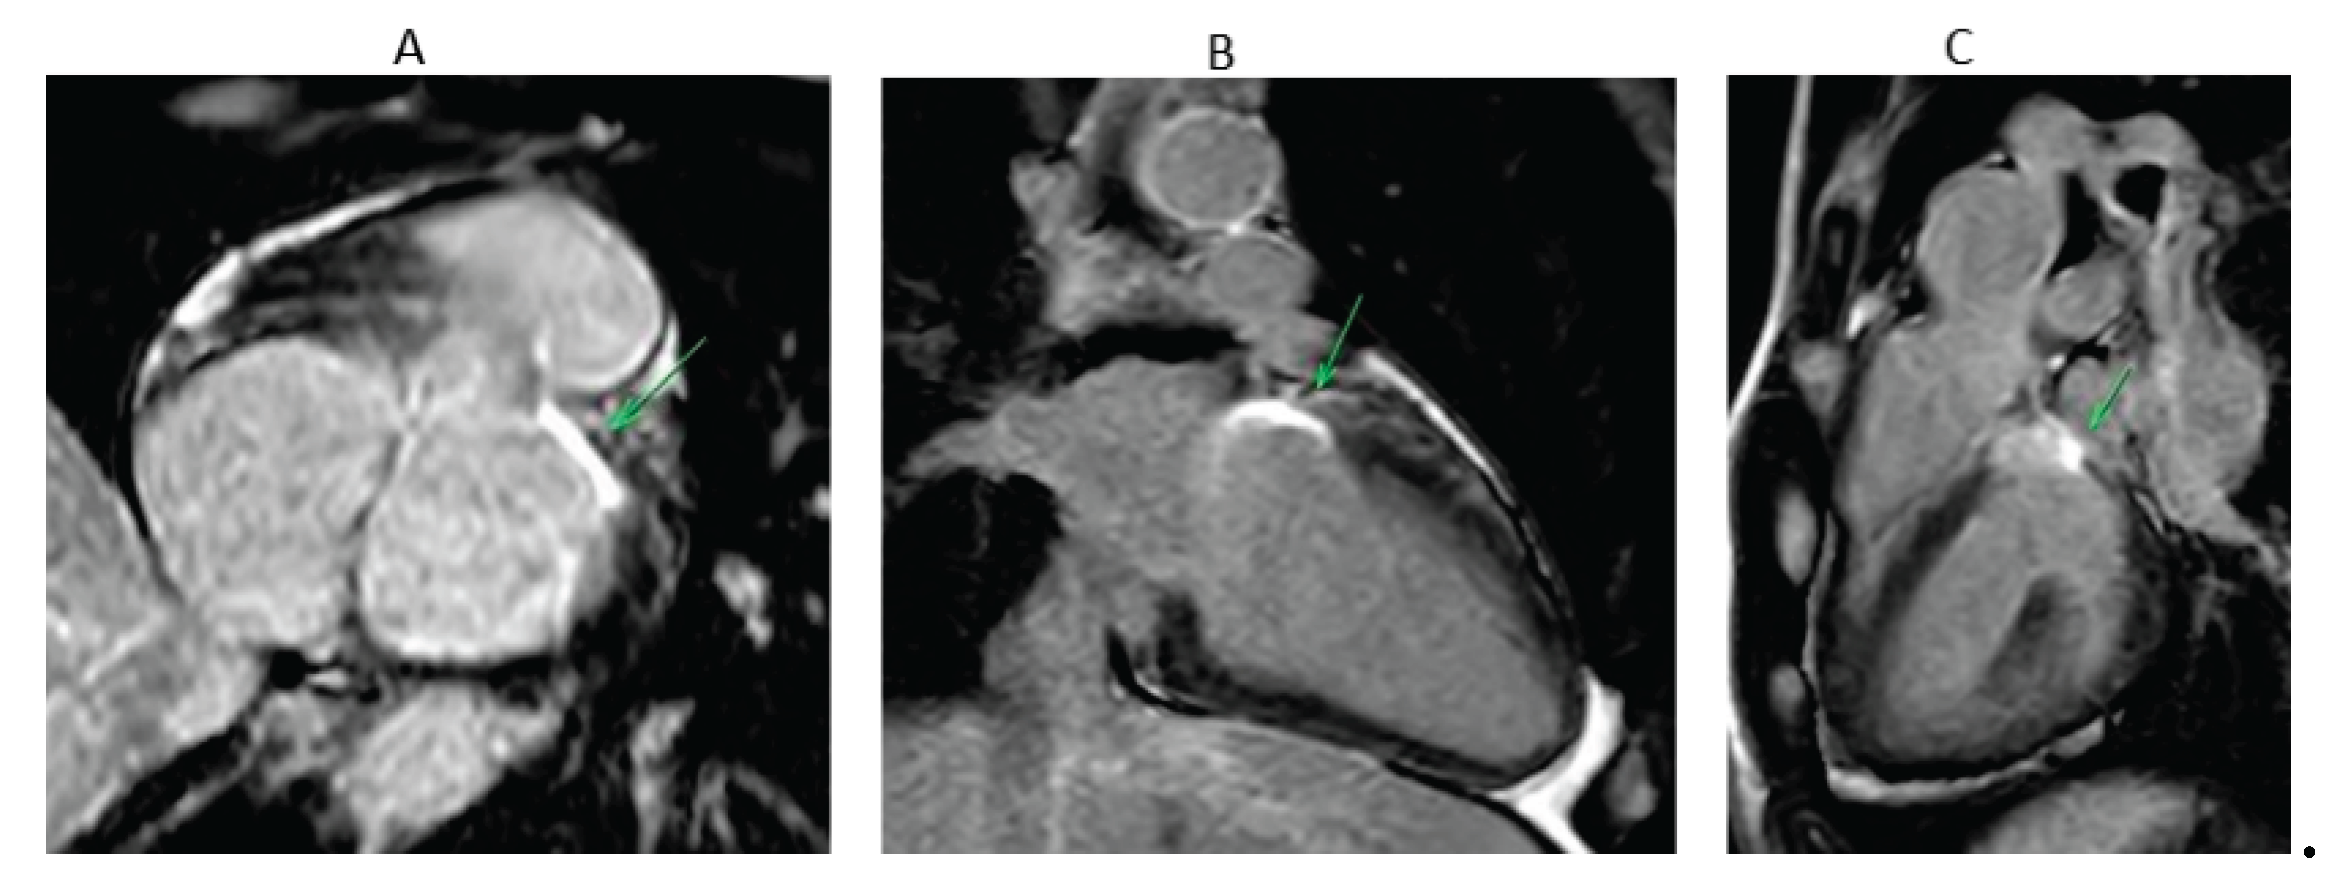

The aim of these techniques is to achieve trans mural lesion that can be detected by cardiac magnetic resonance imaging (MRI) (Figure 4). Preclinical and early clinical studies have shown that late Gadolinium enhancement (LGE)-MRI identified lesion volume and depth correlate with histopathology and, in some cases, with electroanatomic mapping during repeat procedures [41,42]. For LV summit ablation, where catheter stability, contact force, and transmurality are often suboptimal due to anatomical constraints, such imaging may offer valuable insights into long-term lesion durability and efficacy. Although promising, LGE-MRI lesion assessment in the ventricle has yet to be validated as a routine clinical endpoint. For electrophysiologists managing LV summit VA, integrating follow-up LGE-MRI may improve procedural evaluation, guide re-intervention, and refine long-term risk stratification.

Figure 4. MRI images in orthogonal planes from a patient (the patient from Figure 2) who underwent endocardial LVOT prolonged duration ablation for left ventricular (LV) summit ventricular arrhythmia, demonstrating focal transmural late gadolinium enhancement (LGE) at the LV summit—corresponding to the most basal segment of the anterior LV wall. The green arrow highlights the area of LGE. (A) Short-axis view. (B) Two-chamber view. (C) Modified three-chamber view traversing the LV summit.